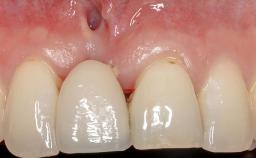

A 30-year-old woman was referred by her general dentist for evaluation of an esthetic complication related to previous implant treatment for congenitally missing maxillary lateral incisors. The patient’s chief complaint was the inadequate esthetic appearance of her smile. The case demonstrates the use of a combined approach to achieve optimal results. Two different flap designs - a tunnel technique and a coronally advanced flap - are employed based on the surgical objectives for the affected site.

Periodontal Plastic Surgery and Prosthetic Procedures to Treat Peri-Implant Soft-Tissue Dehiscences